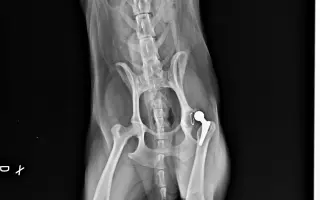

Akutní operace kyčle pro Charlieho: pomozte mu opět běhat bez bolesti